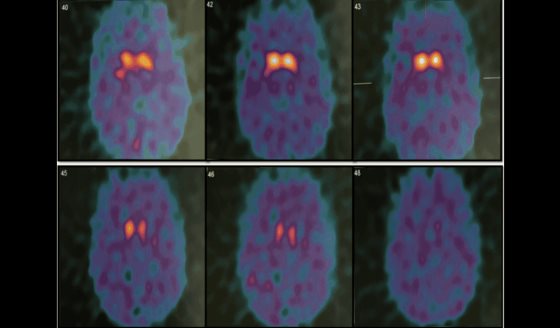

En la mayoría de los casos, la evaluación clínica es suficiente para establecer el diagnóstico. No obstante, existen situaciones en las que pueden surgir dudas diagnósticas, ya sea por atipicidades en la presentación o por comorbilidades del paciente. En esos casos específicos, se puede recurrir a estudios de imagen funcional, como el TAT-scan, una prueba de medicina nuclear.

Tal como explica el especialista: "es una prueba de medicina nuclear en la que se inyecta en el paciente un retroactivo que se pega en las neuronas que tienen dopamina en el cerebro, y eso nos permite saber si el paciente tiene una pérdida de neuronas con dopamina o no".

Sin embargo, aclara que "esto estrictamente no es diagnóstico de párkinson, porque esto ocurre en 4 o 5 enfermedades que se llaman parkinsonismos, y todas ellas comparten este problema, pero sí que nos dirige hacia ese tipo de enfermedad".